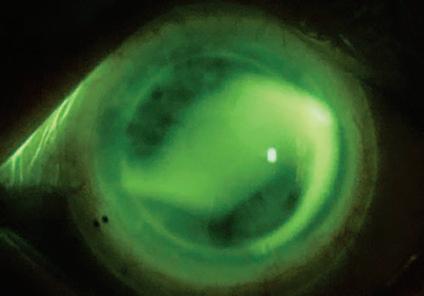

Een 53-jarige man wordt doorverwezen voor een sclerale contactlensaanpassing na een corneatransplantatie van het linkeroog wegens keratoconus. De hulpvraag bestaat uit het verbeteren van het zicht van het linkeroog. De ongecorrigeerde visus OS bedraagt 0,05. Met een brilcorrectie van +1,25 –7,00 x 25 wordt een visus van 0,50 bereikt. Er wordt een diagnostische passing uitgevoerd met een Zenlens® scleralens (Bausch + Lomb) met de volgende parameters: basiskromming (BC) 7.42 mm, diameter 15.4 mm, sagittale hoogte (SAG) 4600 µm en APS flat 2 x steep 2. De overrefractie bedraagt plano –4,00 x 25. Bij beoordeling van de passing werd een superior-nasale randlift gezien, passend bij een licht te vlakke passing. Daarnaast was er sprake van een inferiortemporale decentratie. De hoge cilinderwaarde bij overrefractie wees op toriciteit-geïnduceerde lensflexie. Het fluoresceïnepatroon toonde duidelijke variatie in clearance, passend bij een sterk torisch hoornvlies (Afbeelding 1A). Bij sterk torische corneae kan een onvoldoende vault in bepaalde meridianen leiden tot schijnbare corneale aanraking. Een klassieke benadering is het kiezen voor een grotere diameter en/of grotere sagittale hoogte

BESPREKING

Door toriciteit toe te voegen aan het lenssegment tussen de optische zone en de landingzone kan de lens beter worden uitgelijnd met de cornea, terwijl een sferische basiskromming en eventueel sferische sterkte behouden blijven. Deze passingstechniek staat bekend als Bi-Elevation: gebruik van twee verschillende sagittale hoogtes, overeenkomstig met de twee hoofdmeridianen van de cornea. Bij het beoordelen van de passing dient men de centrale clearance in beide hoofdmeridianen te evalueren: bij voldoende centrale clearance kan de SAG van één meridiaan afzonderlijk worden aangepast, bij onvoldoende clearance dient de SAG in één of beide meridianen te worden verhoogd of verlaagd en tegelijkertijd is de basiskromming aan te passen om de corneale uitlijning te optimaliseren, parallel aan de SAG-aanpassingen. In deze casus werd na setting een centrale clearance van 211 µm gemeten. De bestaande SAG-waarde van 4600 µm bleek voldoende voor de vlakste meridiaan. Om extra clearance te creëren ter hoogte van 4–5 uur en 10–11 uur, werd de globale basiskromming afgevlakt van 7.42 mm naar 8.04 mm, overeenkomend met ongeveer 3,5 dpt. Om de passing in de steilere meridiaan te optimaliseren en de landing beter te laten aansluiten, werd 200 µm extra sagittale hoogte toegevoegd. Dit resulteerde in een lens met Bi-Elevation SAGwaarden van 4600 x 4800 µm. Deze aanpassing maakt de SmartCurve®-zone en de limbal clearance zones steiler in de diepere meridiaan; dit leidt tot een meer regelmatigere midperifere clearance en een stabielere gelijkmatige landing over de volledige omtrek van de lens. De definitieve lens werd ontworpen met de volgende parameters: BC 8.04 mm, SAG 4600 x 4800 µm, diameter 15.4 mm en APS standaard. De passing van de nieuwe lens toonde een passend fluoresceïnepatroon met goede uitlijning en behield dezelfde rotatiepositie als de eerdere torische APS-lens (Afbeelding 1B).

Uitgesproken corneale toriciteit kan het aanpassen van sclerale lenzen bemoeilijken en aanleiding geven tot decentratie, conjunctivale prolaps en zones met zowel overmatige als onvoldoende clearance. Door gebruik te maken van een Bi-Elevation ontwerp kan de corneale toriciteit worden gecompenseerd op het niveau van de sagittale vault. Dit resulteert in een beter uitgelijnde en stabielere sclerale lenspassing.